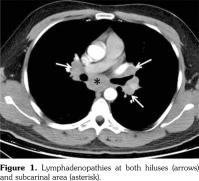

However, pain, dysfunction in daily living activities related with AS, high disease activity markers (erythrocyte sedimentation rate: 53 mm/hour, C-reactive protein: 40 mg/L [normal: 0-6 mg/L], and Bath Ankylosing Spondylitis Disease Activity Index of 6.3 [normal: 0-4]) during the period without etanercept prompted us to consider another anti-TNF-α agent. At the seventh month of etanercept cessation, golimumab with the dosage of 50 mg/month was commenced to compete with the symptoms and findings associated with AS. At the ninth month of follow-up period after inception of golimumab, the patient had no pain with normal disease activity markers. There were no pathological findings regarding sarcoidosis in the examination of the pulmonary system (Figure 3). A written informed consent was obtained from the patient.